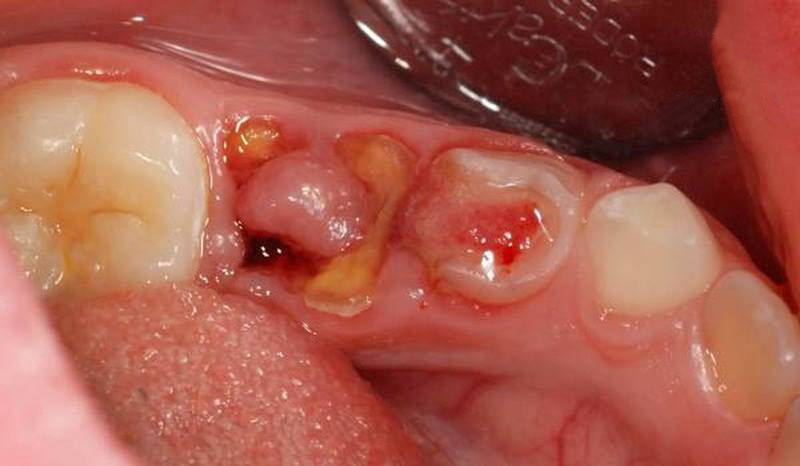

Răng khôn bị nhiễm trùng

- Vị trí nhổ răng bị mưng mủ: là dấu hiệu cảnh báo rõ rệt nhất về sự nhiễm trùng sau khi nhổ răng khôn. Tại vị trí chân răng nhổ bạn sẽ thấy xuất hiện mủ răng có màu trắng hoặc màu vàng kem kèm với biểu hiện nổi hạch ở vùng cổ.

- Xuất hiện chảy máu kéo dài, sưng đau má kéo dài: Khi bạn bị nhiễm trùng vị trí huyệt răng sau khi nhổ răng khôn thì tình trạng chảy máu kéo dài và biểu hiện sưng đau má sẽ diễn ra trong suốt nhiều ngày.